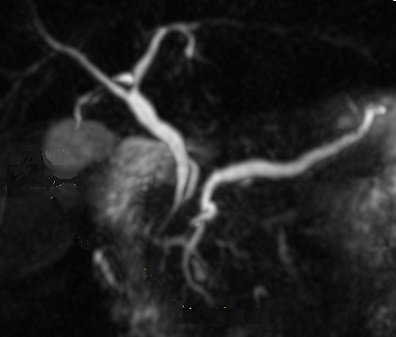

Image radiologique CPRM d'une pancreas

majeur |

Image

absent |